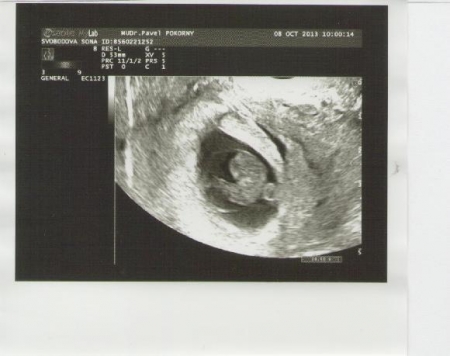

Lékař zjistí důležité údaje týkající se zdravotního stavu ženy i její rodiny. Pečlivé odebrání osobní i rodinné anamnézy je velmi důležité. Zaměřuje se zejména na dědičná onemocnění a stavy, které mohou být komplikací v těhotenství. Následuje gynekologické vyšetření, dle potřeby vyšetření děložního čípku (kolposkopie + onkologická cytologie). V případě obtíží je možno odebrat kultivaci z pochvy a rekta nebo moči. V tomto týdnu je plod v děloze na ultrazvuku dobře patrný, lékař dobře vidí srdeční akci miminka. Na ultrazvukovém vyšetření by měl být stanoven počet plodů a pokud se jedná o dvojčetné/vícečetné těhotenství, pak by mělo být stanoveno, zda se jedná o dvojčata jednovaječná či dvojvaječná. Tato informace je velmi důležitá pro další sledování a ve vyšším stáří těhotenství se také obtížněji určuje.

Zárodek v choriové dutině v 6. týdnu po oplození (8. týden těhotenství). Choriová dutina se jeví jako tmavá, na zárodku se dá dobře rozlišit hlavička a horní končetiny.

Autoři: Texty na základě zdroje www.babyonline.cz, vlastní praxe a znalostí zpracovala MUDr. Jarmila Halová, doplnil a upravil MUDr. Ondřej Šimetka, přednosta Porodnicko-gynekologické kliniky FN Ostrava, obrázky z UZ: MUDr. Radan Doubek, popis k nim: Doc. Šťastná. Poslední korekturu v srpnu 2024 provedla: MUDr. Veronika Ťápalová (Gynekologicko-porodnická klinika LF MU a FN Brno).